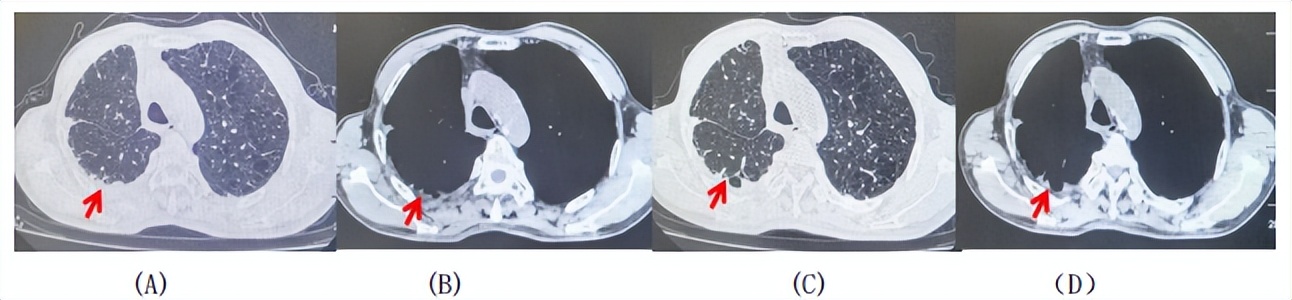

图3:患者免疫联合化疗治疗后胸部CT,(A、B)图展示信迪利单抗联合培美曲塞+卡铂治疗

4周期(2025.02)疗效,(C、D)图展示信迪利单抗+培美曲塞维持治疗6周期(2025.07)疗效